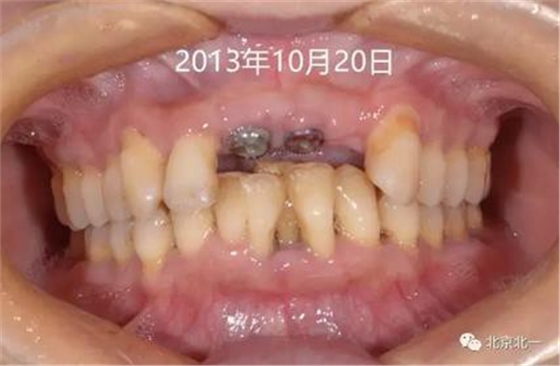

圖八:三年后因牙冠松動脫離復(fù)診, 三年期間沒有復(fù)診。

圖九:2016年10月18日復(fù)查時(shí)照片。